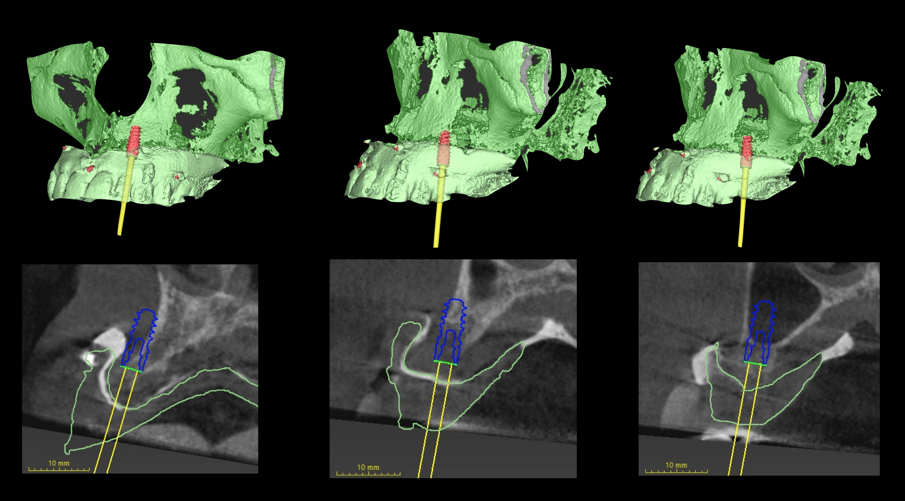

Stabilita la tecnica rigenerativa è necessario fare delle valutazioni sul periodo post operatorio e quindi sul tipo di protesi provvisoria da far indossare alla paziente. Escludendo tutte le tipologie di protesi mobili per almeno sei mesi (compresa quindi una protesi sostenuta da un impianto posizionato nel palato), sempre con l’ausilio del software di chirurgia guidata ho quindi ipotizzato l’inserimento di due impianti nella zona della tuberosità (Fig. 5). Con l’ausilio della dima chirurgica sono stati inseriti tre impianti, due nelle tuberosità mascellari e uno nel palato (Fig. 6). Sui tre impianti è stato progettato insieme ai tecnici un dispositivo in metallo che potesse sostenere dei denti fissi non rimovibili (Fig. 7). Il risultato ottenuto è stato eccellente perché la paziente ha portato una protesi fissa fin dal giorno dell’intervento per tutto il periodo di guarigione, di circa nove mesi. La progettazione della ricostruzione ossea è stata quindi fatta in maniera Protesicamente Guidata, sono stati posizionati gli impianti virtuali e poi valutata l’entità della rigenerazione necessaria.

Una volta ottenute tutte le informazioni necessarie dei dati ossei (Cone Beam), della pianificazione protesica (STL della ceratura, dei tessuti e della situazione iniziale) l’azienda (ReOss, Filderstadt, Germany) invia il progetto della griglia Yxoss CBR che può essere visualizzato in maniera tridimensionale ed eventualmente modificato a discrezione del professionista. Suggerite le eventuali modifiche si esegue la validazione finale del progetto per la realizzazione della griglia (Fig. 8).Con la Customized Bone Regeneration (CBR) l’obiettivo della Rigenerazione Protesicamente Guidata in senso digitale viene così raggiunto. Le griglie sono prodotte attraverso una stampa tridimensionale e il loro fit al difetto è sempre accuratissimo consentendo di concentrare l’attenzione alle altre fasi dell’intervento.

Grazie al flusso digitale, possiamo inserie nel software anche il file STL del provvisorio pre-chirurgico preparato e quindi progettare il provvisorio immediato (Fig. 41). La pianificazione degli impianti a questo punto viene effettuata in modo protesicamente guidato ed è facile posizionare correttamente l’impianto e verificarlo nelle cross del software. Si progetta e si disegna quindi la dima chirurgica (Fig. 42). Il giorno dell’intervento abbiamo già tutto pronto e la paziente presenta uno stato di salute dei tessuti ottimale grazie anche al fatto che ha potuto portare per tutto il periodo una protesi fissa.